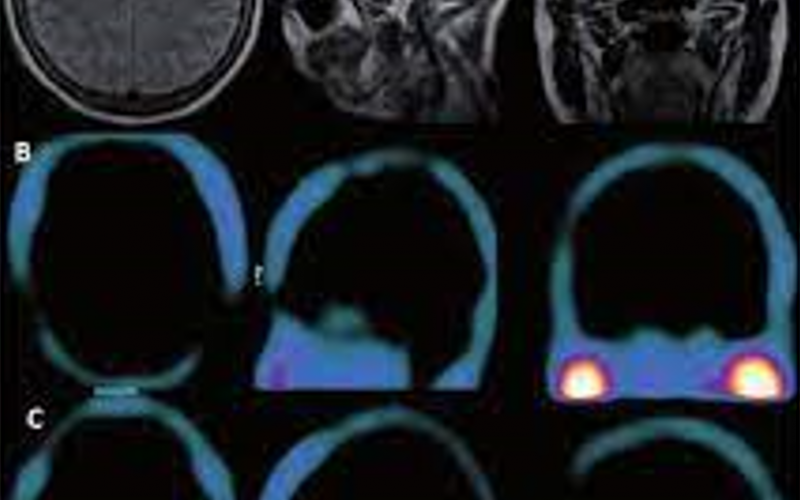

Identificación de lesiones tumorales o metastásicas en tejido cerebral.